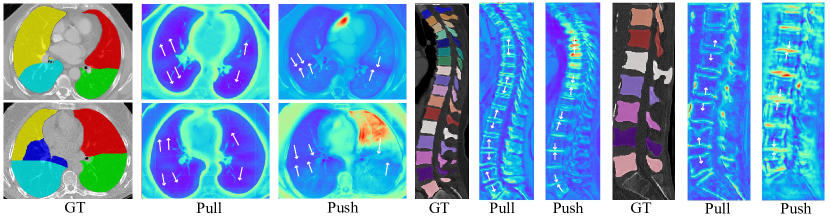

By combining these two modules, the segmentation performance on boundary predictions is further boosted due to adversarial forces. As illustrated in Figure 7, pulling tokens tend to enlarge the inter-class boundary region to amplify the boundary uncertainty, while pushing tokens try to squeeze it. Thus, boundaries between different anatomies are more precisely segmented after reaching the dynamic equilibrium state. Here we pay more attention to the evaluation metric on boundary surfaces. The ASSD value has decreased from 1.674mm to 1.171mm for the clean lung lobe, from 6.210mm to 1.317mm for the fused lung lobe, and from 3.73mm to 3.04mm for the vertebrae. This improvement reveals that adversarial pulling and pushing forces help to more precisely localize uncertain boundaries. However, after introducing CCM to the baseline model with SDM, the segmentation performance for cervical vertebrae declines slightly while thoracic and lumbar vertebrae are finely segmented, which might result from the biased ratio between three kinds of vertebrae [20]. And the same situation comes to the segmentation performance of left lobes. We argue that CCM is essentially effective in clustering five lobes, while class distributions of right lobes are different from those of left lobes. And neural networks exert the boundary shape constraint of right lobes to left lobes due to the class imbalance. Furthermore, Figure 9 exhibits the ablation visualizations for key components with a vertebral CT case. Adding SDM and CCM achieves a finer and more consistent prediction, especially for boundaries.